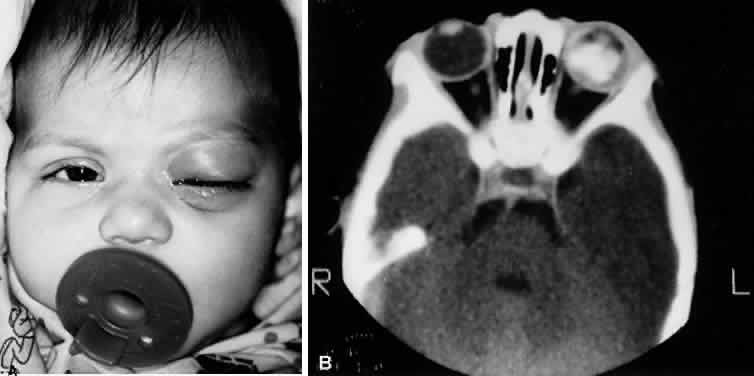

Cavernous sinus thrombosis is a dreaded complication of paranasal sinusitis. It may be difficult to distinguish from simple orbital cellulitis and may occur with and secondary to orbital cellulitis. Cavernous sinus thrombosis most commonly results from anterograde venous spread from and infection involving the middle third of the face, including the mouth, orbit, and paranasal sinuses. Retrograde spread of infection to the cavernous sinuses from the posterior aspect of the mouth, pharynx, middle ear, and mastoid air cells may occur, but is uncommon. A patient with cavernous sinus thrombosis but without orbital cellulitis will show marked restriction of ocular motility out of proportion to the degree of proptosis, will have normal retropulsion of one or both globes, hypesthesia in the distribution of the ophthalmic and maxillary divisions of the trigeminal nerve, dilated retinal veins, orbital congestion, and possibility altered sensorium and other neurologic deficits. A cranial MRI can help confirm the diagnosis of cavernous sinus thrombosis.51 Orbital pseudotumor occurs predominantly in older age groups. Orbital congestion, proptosis, and limitation of motility may develop rapidly. Orbital echography may be helpful in the differentiation.52 Orbital myositis can involve one or more extraocular muscles, and may produce mild vascular congestion and proptosis. A rapidly growing necrotic retinoblastoma can cause enough local inflammation to simulate either orbital or preseptal cellulitis (Fig. 22). Rhabdomyosarcoma can cause proptosis with distention of the lids and orbit (Fig. 23). Metastatic orbital tumor can cause similar findings, especially metastatic breast carcinoma. Endocrine ophthalmopathy can usually be identified by its typical clinical features.